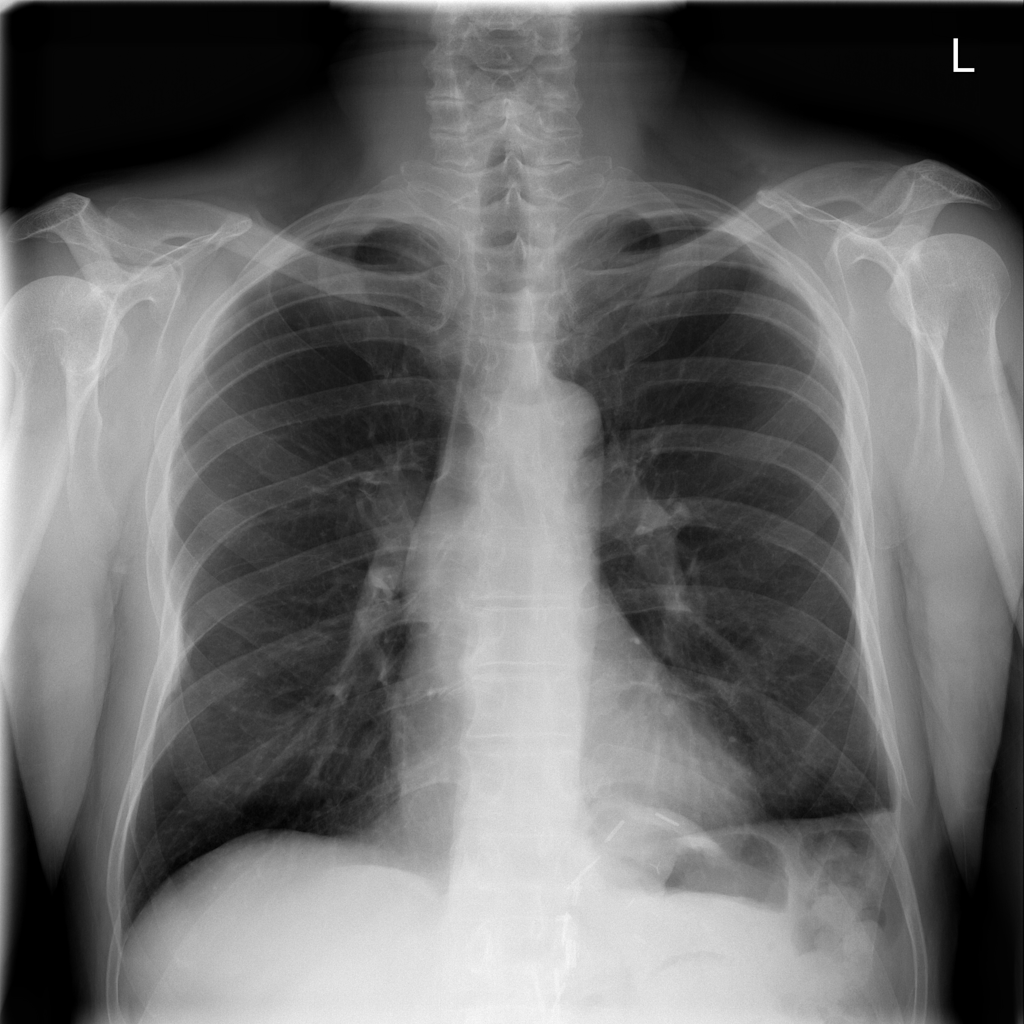

Showing up to 90 reference images for Hernia.

PAT-C048 · IMG-000Hernia

PAT-C048 · IMG-000

PA